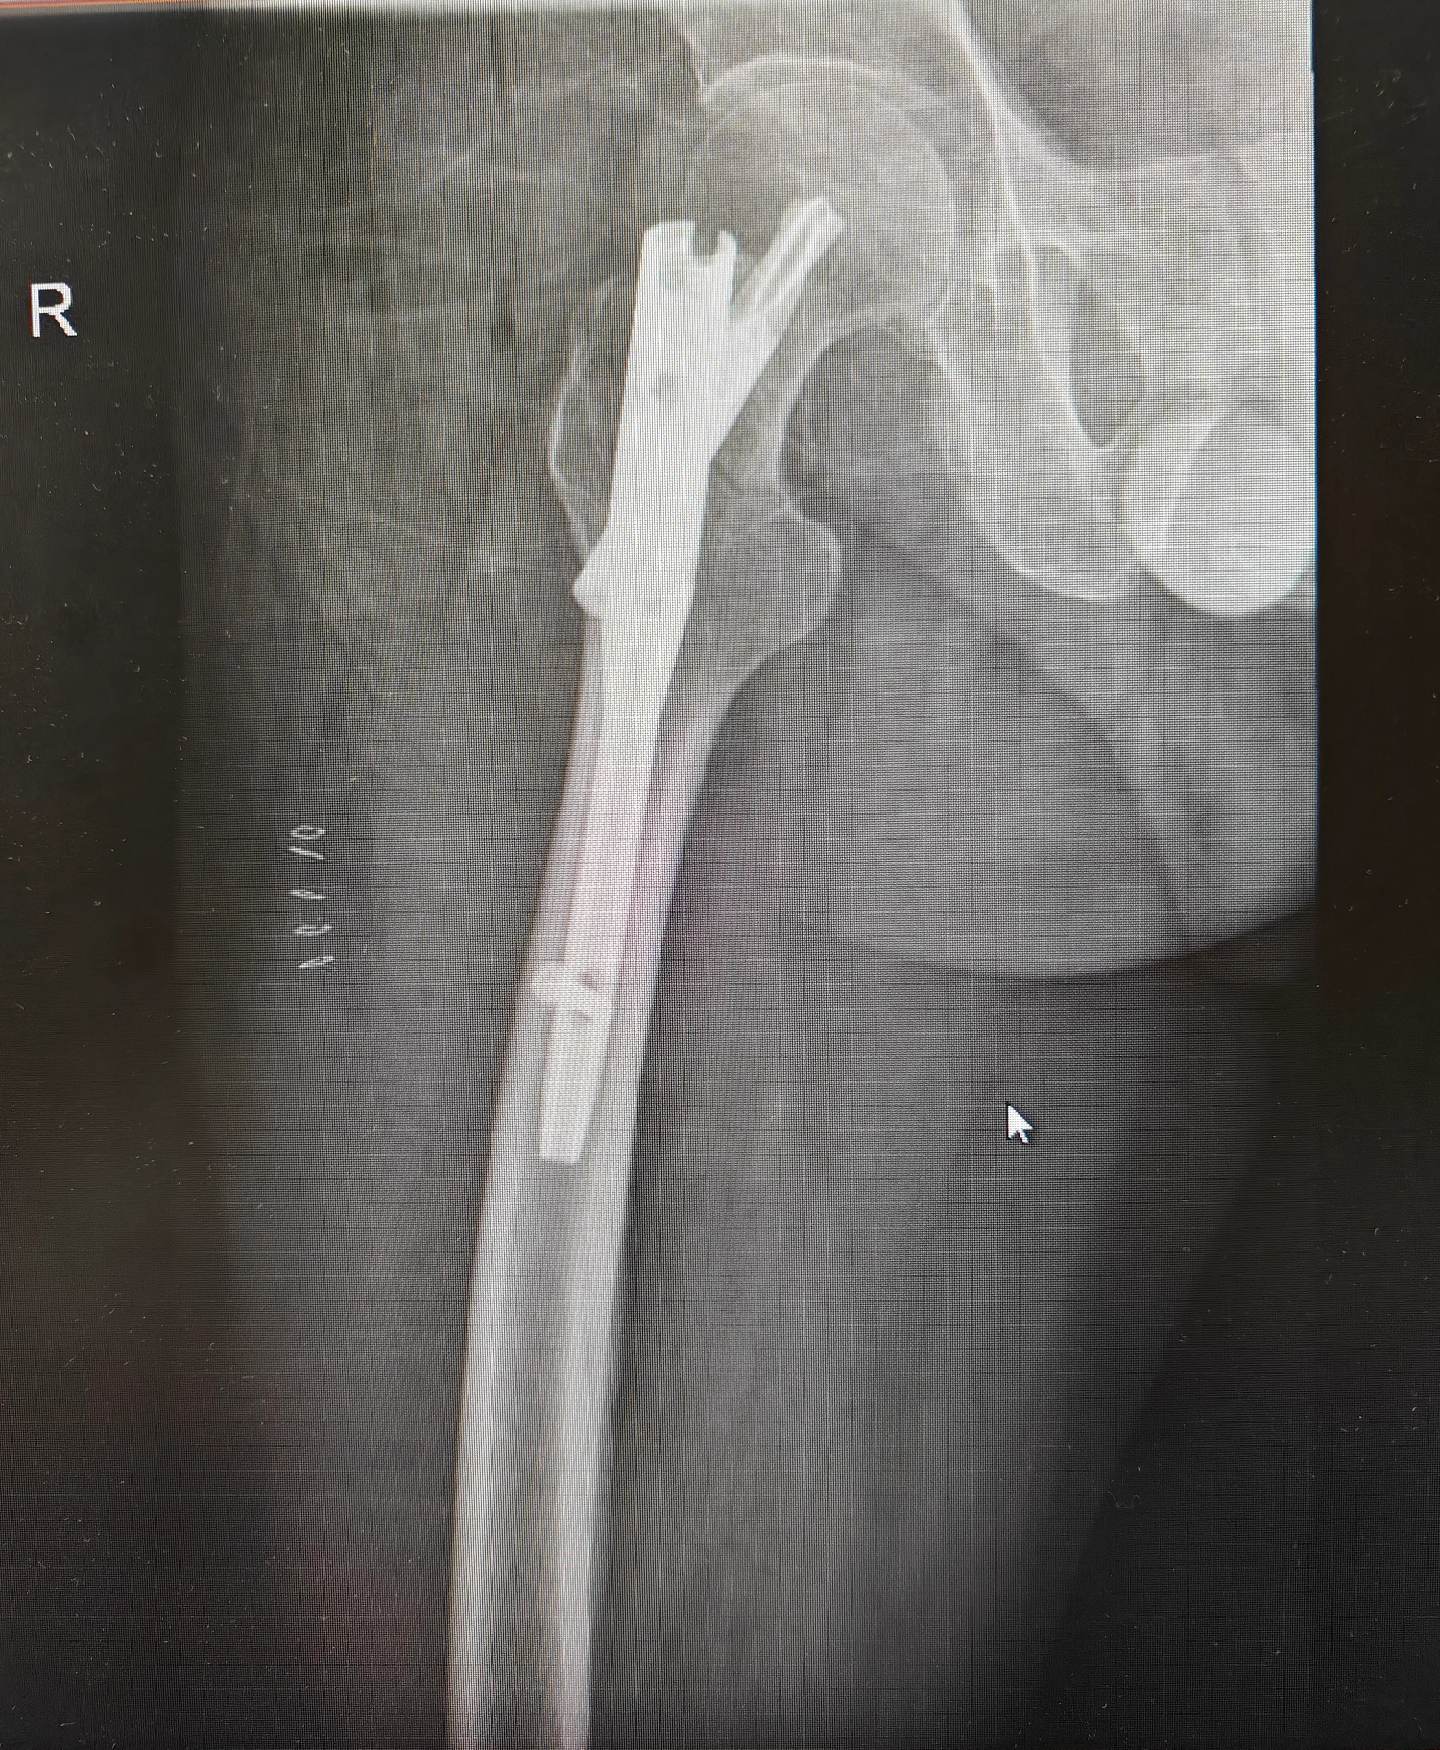

股骨颈骨折。老年体弱股骨颈骨折患者,人工股骨头置换可以使其立即下床,但对于脑梗塞后遗症,肌力小于3级的病人并不适合,所以这例患者使用了PFN。为病人选择最合适的、最受益的手术方式是外科医生的追求🌹